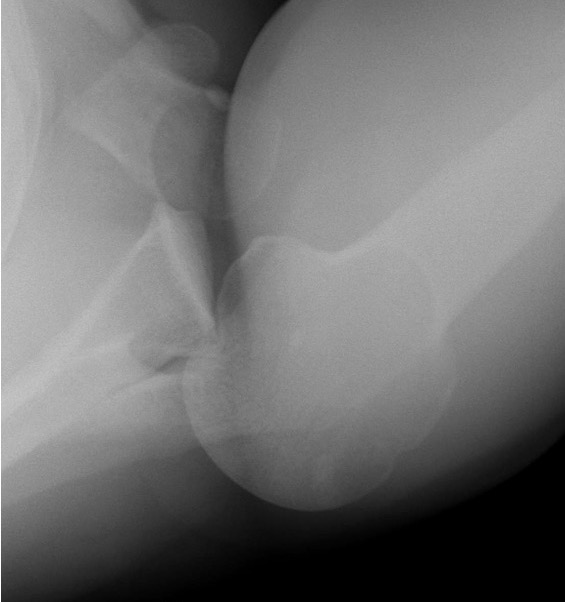

Scapular lateral

Center of the humeral head must be centered on the Y / Mercedes sign

Y is formed by

- coracoid anteriorly

- scapular spine posteriorly

- scapula body inferiorly

Normal scapular lateral

Posterior shoulder dislocation

Posterior shoulder dislocations